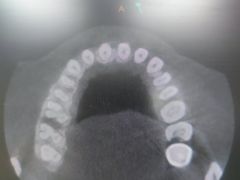

• 民航总医院

• -民航总医院